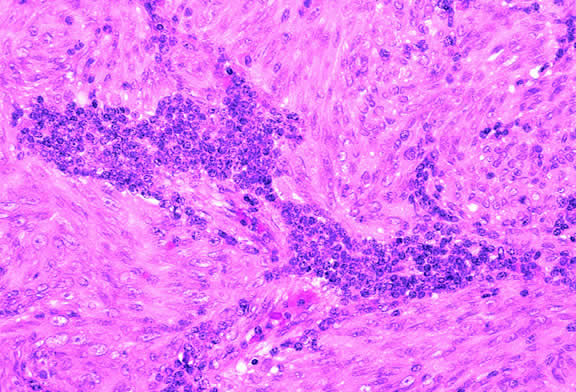

Histopathology

The cells comprising uveal melanoma constitute a biologic spectrum comprising bland spindle A melanoma cells at one end and wildly anaplastic epithelioid cells at the other. The term spindle cell is derived from the fusiform or spindled configuration of the cells' cytoplasmic outline. They are bipolar in shape, and many have long tapering processes that occasionally are highlighted when individual pigmented cells are seen in a largely amelanotic tumor. Spindle cells grow in a syncytial fashion forming interweaving fascicles of parallel oriented cells (Fig. 30). The cells can be pigmented or nonpigmented. Two types of spindle cells are recognized; spindle A and spindle B. These are distinguished by their nuclear characteristics. Spindle A nuclei are tapering ovals or cigar-shaped and have finely dispersed chromatin (Fig. 31). If a nucleolus is present, it usually is inconspicuous. Many spindle A cells have a longitudinally oriented chromatin stripe that actually is caused by a fold in the nuclear membrane. The nuclei of spindle B cells have distinct nucleoli and coarser chromatin and tend to be plumper and more oval in shape (Fig. 32).

Fig. 30. Amelanotic spindle cell melanoma. Tumor is composed of interweaving fascicles of spindle cells. Photomicrograph shows longitudinally and transversely sectioned fascicles. (Hematoxylin-eosin, × 100.)

Fig. 31. Low-grade spindle melanoma. Spindle A cells have bland, slender, cigar-shaped nuclei with finely dispersed chromatin and indistinct nucleoli. Longitudinal folds in the nuclear membrane are apparent microscopically as a chromatin stripe or line. Bland spindle B nuclei with distinct nucleoli also are present. (Hematoxylin-eosin, × 250.)

Fig. 32. Spindle B melanoma cells. Most of the cells in this field are spindle B melanoma cells. They have oval nuclei and an obvious nucleolus. Compared with spindle A cells, their chromatin is more coarsely clumped. The spindle cells form a syncytium and have indistinct cytoplasmic margins. (Hematoxylin-eosin, × 250.)

Epithelioid melanoma cells comprise the poorly differentiated end of the cytologic spectrum. Melanomas that contain epithelioid cells have a poorer prognosis. The term epithelioid meaning epithelial-like reflects the fanciful resemblance of the tumor cells to the cells of simple epithelia. Epithelioid cells have abundant cytoplasm and are often polygonal in shape (Fig. 33). They have distinct cytoplasmic margins, are poorly cohesive, and do not grow as a syncytium. The nuclei of epithelioid cells are usually round or oval and often appear vesicular because of margination or clumping of the chromatin along the inner side of the nuclear membrane. Epithelioid melanoma cells also have prominent nucleoli that are often large and reddish purple. Variants of epithelioid cells include relatively uniform small epithelioid cells (Fig. 34) and bizarre tumor giant cells that may appear wildly anaplastic (Fig. 35).

Fig. 33. Epithelioid melanoma cells. The cytoplasmic margins of these large, poorly cohesive epithelioid melanoma cells are easily discernible. Epithelioid cell nuclei are typically round and have peripheral margination of coarsely clumped chromatin. Epithelioid cells usually have prominent reddish purple nucleoli. They typically are polyhedral in shape and have copious amounts of cytoplasm. (Hematoxylin-eosin, × 250.)

Fig. 34. Small epithelioid cells. Cells are relatively small but are definitely epithelioid in character. They are polyhedral in shape and have distinct cytoplasmic outlines. The round nuclei contain prominent nucleoli. (Hematoxylin-eosin, × 250.)

Fig. 35. Tumor giant cell, uveal melanoma. Tumor giant cells are highly anaplastic epithelioid cells. They are relatively rare, and their prognostic significance is uncertain. (Hematoxylin-eosin, × 100.)

Melanoma cells should be classified by their nuclear characteristics. Spindle-shaped cells that have epithelioid nuclei occasionally are encountered; such cells are classified as epithelioid. In recent years, the term intermediate cell has been used increasingly. Intermediate cells are cells that have nuclear characteristics that are intermediate between spindle B and epithelioid. For example, one might apply the term intermediate cell to a spindle B cell that has a nucleus that is somewhat large and has a fairly prominent nucleolus.

Melanocytic tumors of the uvea are classified into four groups on the basis of cytology. Tumors composed entirely of spindle A cells or even blander nevus cells are classified as spindle cell nevi. Tumors composed of a mixture of malignant spindle A and spindle B cells are called spindle melanomas. Melanomas of mixed cell type contain a mixture of spindle and epithelioid melanoma cells (Fig. 42). Some laboratories specify the predominant cell type found in a mixed cell melanoma, for example, reporting mixed cell, predominantly spindle if only a few epithelioid cells are present. Epithelioid melanomas are composed predominantly of epithelioid cells. They are relatively rare and have the poorest prognosis. Most medium- and large-sized melanomas contain a mixture of spindle and epithelioid cells. In the COMS histopathology study, 86% of the posterior melanomas were classified as mixed cell type, 8% were of spindle cell type, and 5% were epithelioid.84 The association between cytology and mortality is known as the Callender classification.90 (See later section on prognostic factors.)

Fig. 42. Uveal melanoma, mixed cell type. Mixed cell melanomas are composed of a mixture and spindle and epithelioid cells. (Hematoxylin-eosin, × 250.)